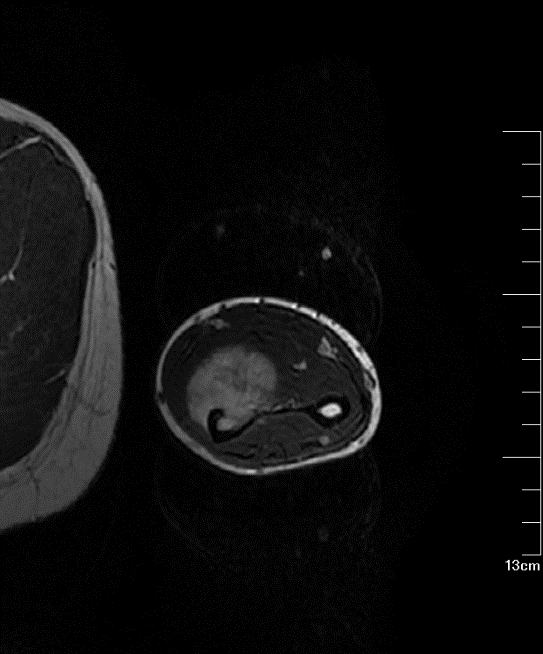

17岁的小贝,发现左前臂右肿块2个多月,因近期肿块处有明显增大及疼痛加强,遂前往肿瘤医院骨科门诊就诊。肿瘤医院骨科王伟东副主任接诊后详细询问了小贝的发病经过,并仔细地做了体格检查。从病人的主诉加上MRI检查结果提示恶性肿瘤的可能性大。

▲ 患者初诊MR

在征取患者与家属同意后予安排对病灶经皮穿刺活检,以明确肿瘤性质,后续病理检查提示:左前臂中段尺侧腺泡型横纹肌肉瘤。

横纹肌肉瘤是横纹肌细胞或横纹肌细胞分化的间叶细胞的一种恶性肿瘤,一种好发于青少年和儿童的恶性肿瘤,主要表现痛和无痛性肿块,肿块破溃出血。有5种亚型,本次我科收治的腺泡状 横纹肌肉瘤(Alveolar Rhabdomyosarcoma,ARMS)是其中之一,具有较强的侵袭性,且易浸润和转移,在横纹肌肉瘤的5中亚型中预后较差。该患者肿瘤位于患者的左前臂尺侧掌面,位于指深屈肌深面,左侧尺骨干中段已经出现了骨质破坏,肿瘤侵入髓内。手术治疗难度非常大。